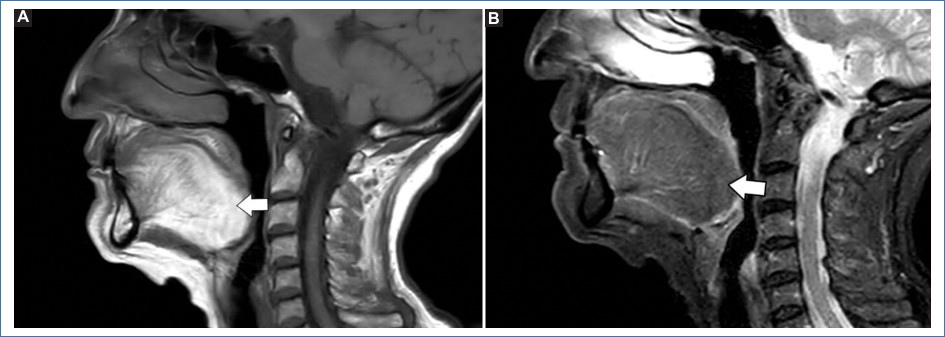

La afectación de los músculos de la lengua genera depósito de lípidos junto a hipoatrofia, mostrando hiperintensidad característica en secuencias ponderadas en T1. Esta particularidad se denomina signo de “la lengua brillante” (bright tongue)9,10. El diagnóstico diferencial debe realizarse con otras enfermedades neuromusculares, como esclerosis lateral amiotrófica, distrofias miotónicas tipo I, miositis con cuerpos de inclusión, etc.9,10 (Fig. 2).

La secuencia ponderada en T1 permite estudiar el grado de infiltración grasa en los músculos, mientras que las secuencias T2 y STIR valoran la presencia de edema muscular8 (Fig. 1).